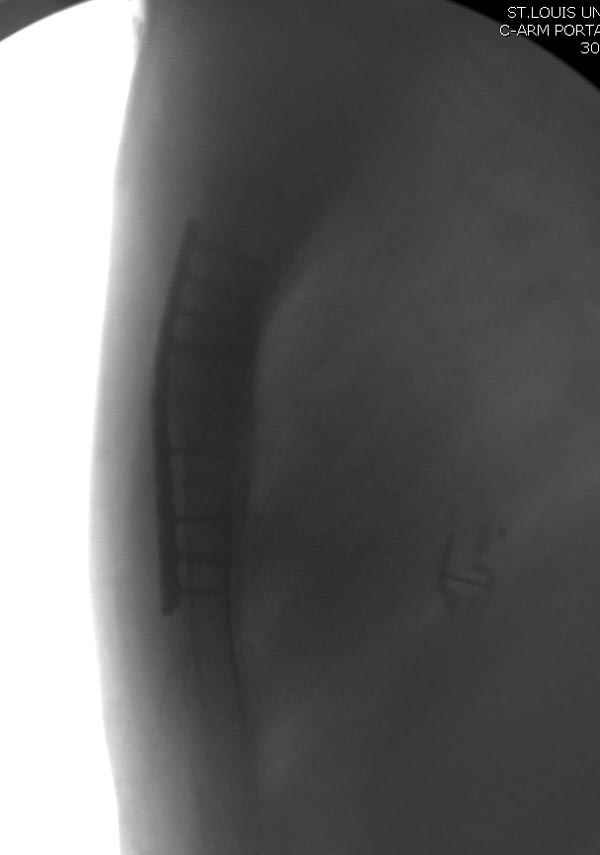

Оперировали вместе с грудным хирургом и в нашем случае главной причиной была болезненность. Во время операции приняли все меры предосторожности недопущения прокола средостения (см. на 4 снимке близкий контур сердца!!)

Ложный сустав зафиксирован двумя пластинами 2.4 мм (locking plate) позаимствованными из челюстно-лицевой хирургии, с костной пластикой, все остальные пластины мне показались слишком толстыми, грубые для грудины или отсутсвовали возможности создания угловой стабильности.

Рентген снимки во время операции и последние сделаны на днях.